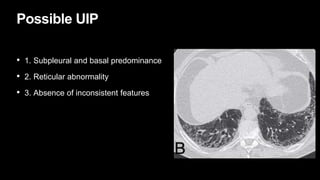

Possible UIP

• 1. Subpleural and basal predominance

• 2. Reticular abnormality

• 3. Absence of inconsistent features